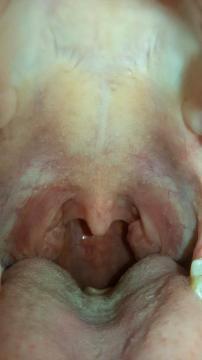

Pro větší náhled klikněte na obrázek

Mám něco asi něco s mandlema Mikulandrova - 16.9.2014 16:35:33

Dobrý den, prosím pomozte mi co to mám, jestli je to normální nebo ne:-( nemám je mi dobře, jen mě občas bolí hlava a polykání

Vaše mandle vypadají být v pořádku.